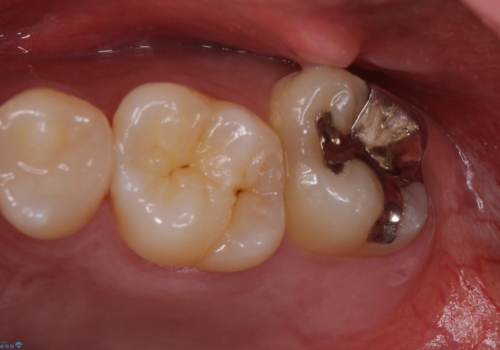

- 銀の詰め物のやり替えを主訴に来院されました。

歯の奥が歯ぐきに埋もれている状態であったため、埋まっている親知らずを抜歯しつつ歯茎の高さを落とし、外れにくいジルコニアクラウンを装着していきます。

- 左上7 歯肉切除:5,500円/仮歯:11,000円/ジルコニアクラウン:110,000円費用は治療当時の料金となります